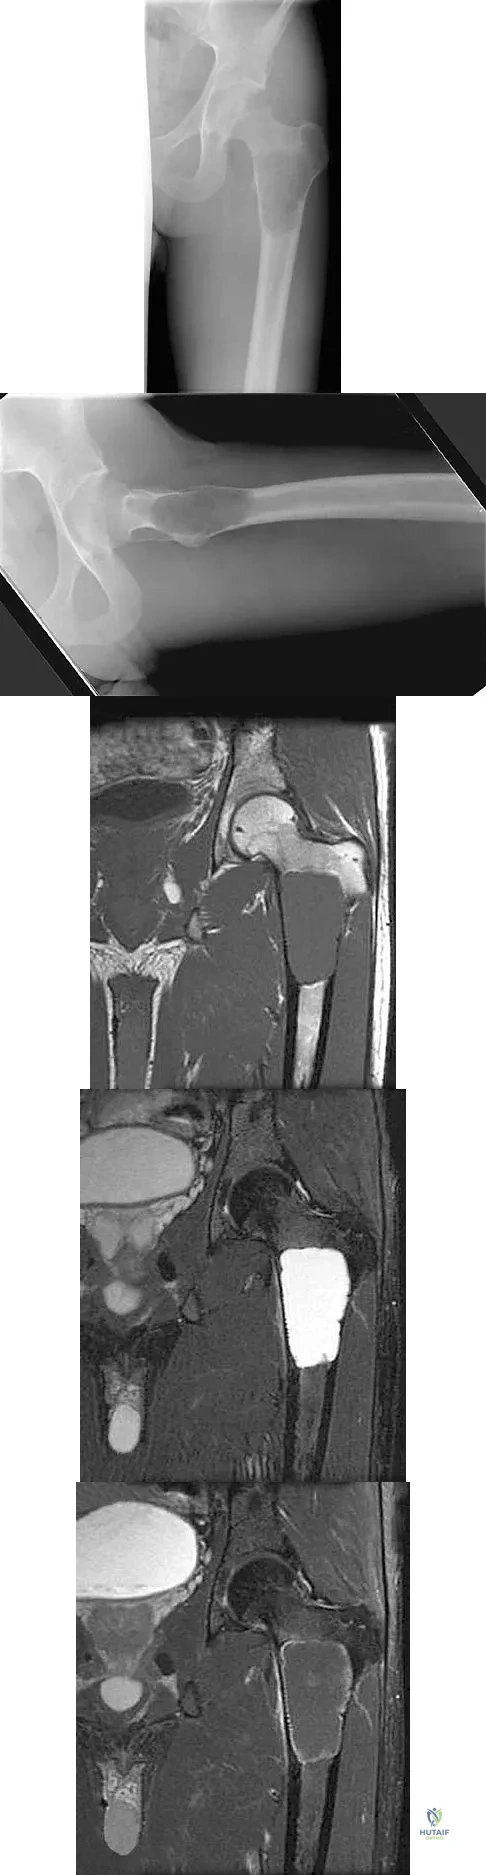

Question 100

A 16-year-old girl has had pain in the left groin for the past 4 months. She notes that the pain is worse at night; however, she denies any history of trauma and has no constitutional symptoms. There is no history of steroid or alcohol use. Examination reveals pain in the left groin with rotation of the hip. There is no associated soft-tissue mass. A radiograph and MRI scan are shown in Figures 32a and 32b, and biopsy specimens are shown in Figures 32c and 32d. What is the most likely diagnosis?

Explanation